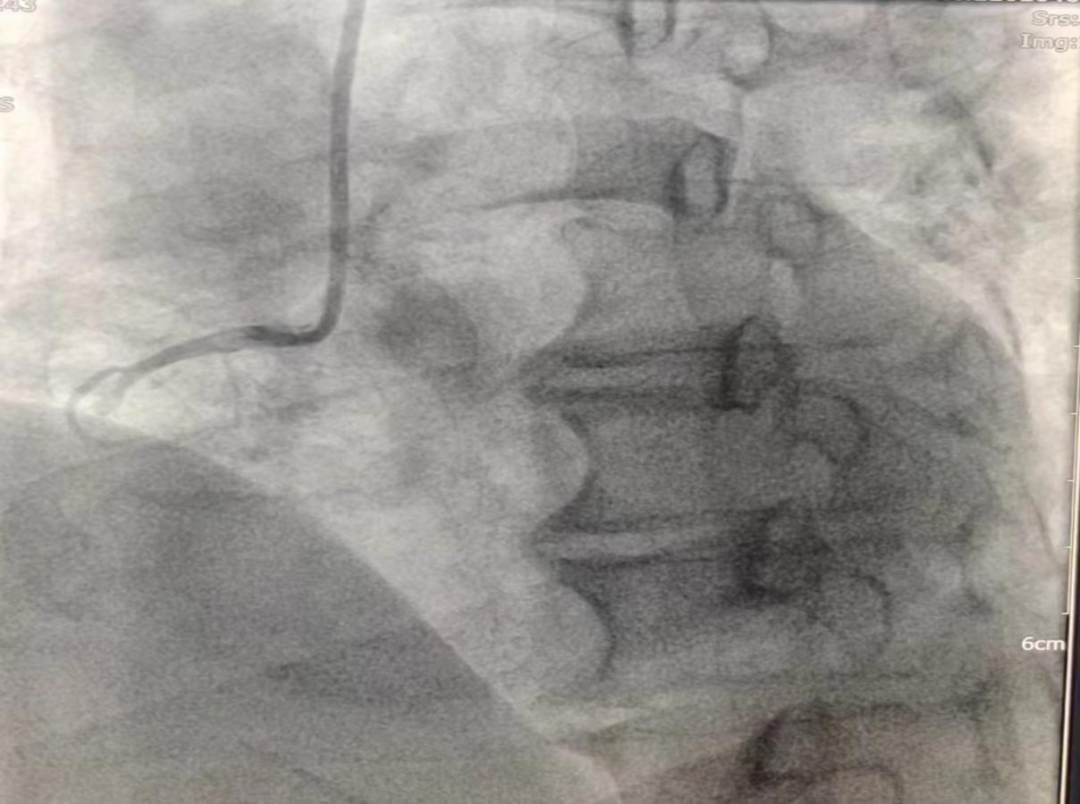

(圖為生物可吸收支架置入術后影像)

女性患者,49歲,突發暈厥急診我院,經診斷為:冠狀動脈粥樣硬化性心臟病、2型糖尿病。導入造影導管行冠狀動脈造影示:冠狀動脈分布呈左冠優勢型,LM未見明顯狹窄,血流TIMI3級;LAD全程多發斑塊,中段狹窄約60%,遠端狹窄約50%,D1未見明顯狹窄,血流TIMI3級;LCX未見明顯狹窄,血流TIMI3級,RCA近端狹窄約50%,中段發出圓錐支后完全閉塞,血流TIMI0級,急診開通血管并充分擴張,殘余狹窄仍然嚴重。在與患者及家屬溝通時,其了解得知臨床有一種新型的可吸收支架,植入體內后支架能完全被降解和吸收,希望能用這種新型的支架進行手術治療。由于生物可吸收支架有著嚴格的適應癥,因此經過嚴格篩選評估,最終對患者進行了Xinsorb生物可吸收支架置入術。支架植入術前經過充分預擴張,按照規范的可吸收支架操作流程,快速送入可吸收支架到病變部位,精準定位后14個大氣壓釋放,生物可吸收支架后擴球囊擴張。充分球囊后擴張,以保證支架貼壁良好,血流速度正常,造影完美,手術順利結束。